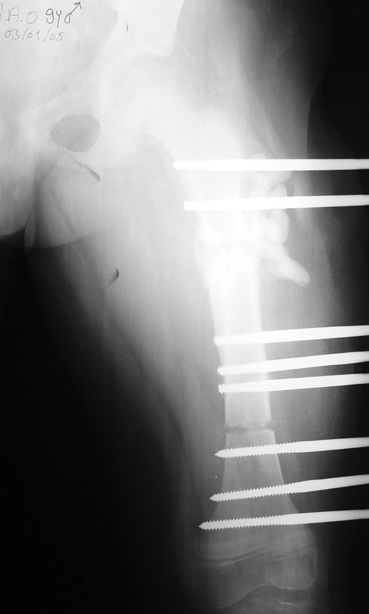

Appropriate radical debridement necessitates excision of all necrotic bone and soft tissues, and frequently causes instability at the involved extremity. The remaining bone and soft tissue defect has to be fixed and reconstructed. The distraction osteogenesis method of Ilizarov is used successfully for achievement of union, correction of the deformity, elimination of limb length inequality and reconstruction of segmental bone defects.

The duration of external fixation (external fixation index) depends on the amount of distraction required, and the extremity is prone to complications during this period. After the distraction phase is completed, the external fixator remains in place during the consolidation phase, which lasts twice as long as the distraction phase; but this period is hardly tolerated. If the external fixator is removed before sufficient consolidation is achieved, fractures, deformity and shortness will be the result. In our department, ‘lenghthening over nail’ method is used in order to decrease the external fixation index and increase patient comfort and activity level. In this method, the intramedullary nail is statically locked after the completion of the distraction phase, and external fixator is removed. The extremity is stabilized by the intramedullary nail during consolidation phase. In this way, complications due to long external fixation index or early removal of the external fixator are avoided.

Case 3